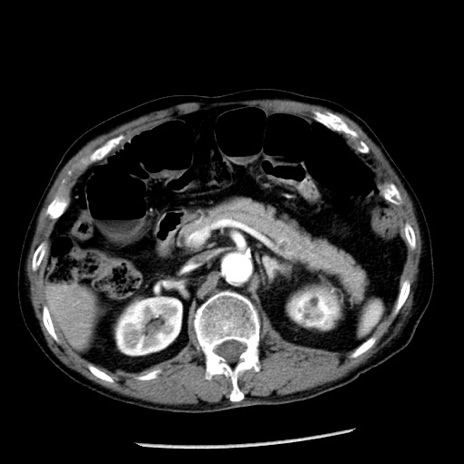

症例26(横断像)

【症例】80歳代男性

【主訴】嘔吐

【現病歴】昨晩2回嘔吐あり、今朝になっても嘔吐あり。来院。

【既往歴】胃潰瘍

【身体所見】意識清明、BT 37.6℃、BP 166/95mmHg、HR 100bpm、SpO2 97%、腹部:平坦・軟、腸蠕動音聴取良好、圧痛なし。

【データ】WBC 21900、CRP 1.46